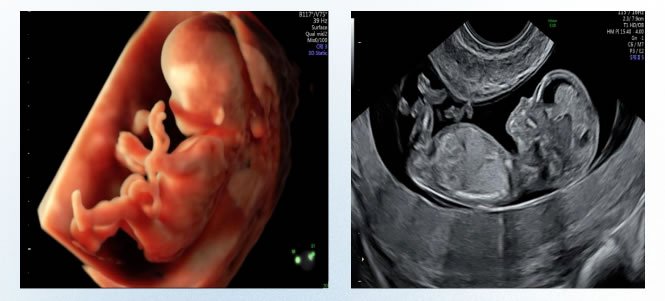

超聲醫(yī)學(xué)科是江蘇省首批認定的(de)產前診斷機構,是徐州地區產前超聲篩(shāi)查診斷機構的歸口單位,承擔著淮(huái)海經濟(jì)區疑難危重(chóng)婦(fù)產科(kē)疾病、新生兒心髒超聲篩(shāi)查診斷及會診工作,產(chǎn)前超聲篩查和(hé)診斷技術領跑淮海經濟區,為淮海經濟區婦產科超聲龍頭單位。

科室年檢查量(liàng)30餘萬(wàn)人,日檢查量800-1200人次,2016年被評為徐州市級臨床重點專科。全科共有醫護人員40餘名,技術力量雄厚。其中,碩士研究生14人(rén),高級職稱13人,多人在省、市級學會任職。

在(zài)學(xué)科帶頭人(rén)左(zuǒ)雲鵬主任的帶領下,超聲科技術力量雄厚,人員素質過硬,開展包括腹部、淺表(biǎo)、婦(fù)產、泌尿、心髒、血管及新生兒顱腦、髖關節等全身各器官的超聲(shēng)檢查項目。其中,胎兒係統篩查、胎兒畸形診斷、胎兒心髒以(yǐ)及新生(shēng)兒顱腦、心髒、髖關節、盆底超聲等(děng)檢查尤具特色,產前診斷水平處於國內領(lǐng)先水平,並率先在本市開展了女性(xìng)盆底、婦科三維、四維(wéi)超聲、子宮(gōng)輸卵管造影等檢查。